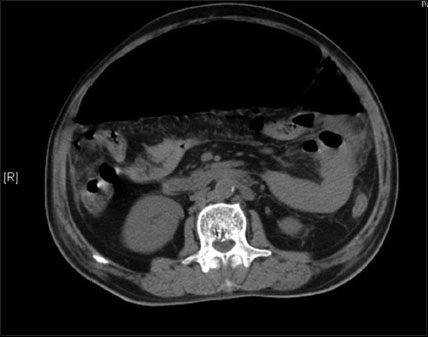

The patient was given antibiotic treatment with injection colistin, tigecycline, meropenem, and linezolid. Tablet ivermectin was added 12 mg, two doses, 14 days apart.[7] The patient developed acute abdomen during hospitalization. The liver and renal function tests were deranged with an increase in C-reactive protein to 64 mg/dl and procalcitonin >10 ng/ml. Total white cell count was normal, but the differential count showed increased neutrophils: 91.6% (40.0–80.0) with low lymphocytes: 4.8% (20.0–40.0) and eosinophils: 0.4% (1.0–6.0). Hemoglobin was low at 8.2 g/dL (12.0–15.0). Computed tomography abdomen showed intestinal perforation [Figure 2]. Exploratory laparotomy was performed which revealed gastric and jejunal perforations. The gastric perforation edge biopsy revealed yeast and pseudohyphal forms (likely Candida spp.). Jejunal perforation edge tissue biopsy showed fungal hyphae suspicious for mucormycosis. Peritoneal fluid sent for culture grew Candida tropicalis sensitive to amphotericin B, caspofungin, micafungin, fluconazole, and voriconazole with minimum inhibitory concentrations of ≤0.25, ≤0.25, ≤0.06, ≤1, and ≤0.12 μg/ml, respectively. Peritoneal fluid also grew VRE Enterococcus faecium sensitive only to linezolid. Five days later, blood culture grew Candida glabrata sensitive only to amphotericin B and micafungin. The patient was administered liposomal amphotericin B and caspofungin. However, the patient continued to deteriorate clinically and succumbed to the multiple infections 17 days after the perforation.

| Figure 2 Computed tomography abdomen of the patient showing pneumoperitoneum